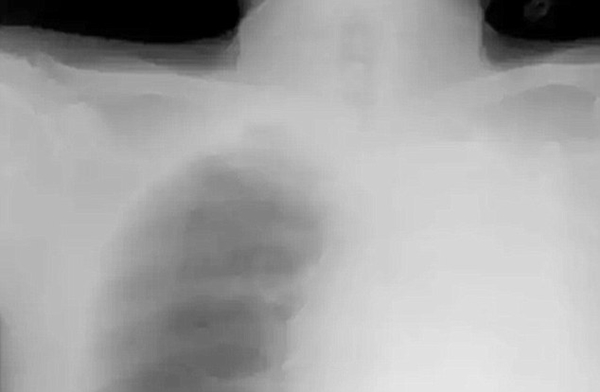

หลังจากผลเอกซ์เรย์ปรากฏออกว่าปอดซ้ายของเขาอันตรธานไปทั้งหมด ในทีแรกก็คิดว่าปอดซ้ายของเขาอาจจะถูกครอบงำด้วยเนื้องอกขนาดใหญ่ก็ได้ จึงทำการผ่าตัดไขปริศนา และเมื่อผ่าตัดแล้วก็ถึงบางอ้อเมื่อพบว่า ต้นตอของ "ปอดหาย" ไม่ใช่เนื้องอกอย่างที่คาดไว้ แต่เป็นปลอกปากกาเล็ก ๆ เข้าไปอุดตันหลอดลมที่เชื่อมไปยังปอดซ้าย จึงได้ถามไถ่นายหยู หัง ว่าเกิดอะไรขึ้นกับเขา ปลอกปากกาเข้าไปอยู่ในนั้นได้อย่างไร

อย่างไรก็ดี ศัลยแพทย์สามารถผ่าตัดเอาปลอกปากกาออกมาจากปอดของหยู หัง ได้สำเร็จ แต่นั่นก็ไม่สามารถทำให้ปอดซ้ายของเขากลับมาทำงานได้ดังเดิม เพราะมันเหี่ยวแฟบไปแล้ว

ภาพจาก Sir Run Run Shaw Hospital School of Medicine